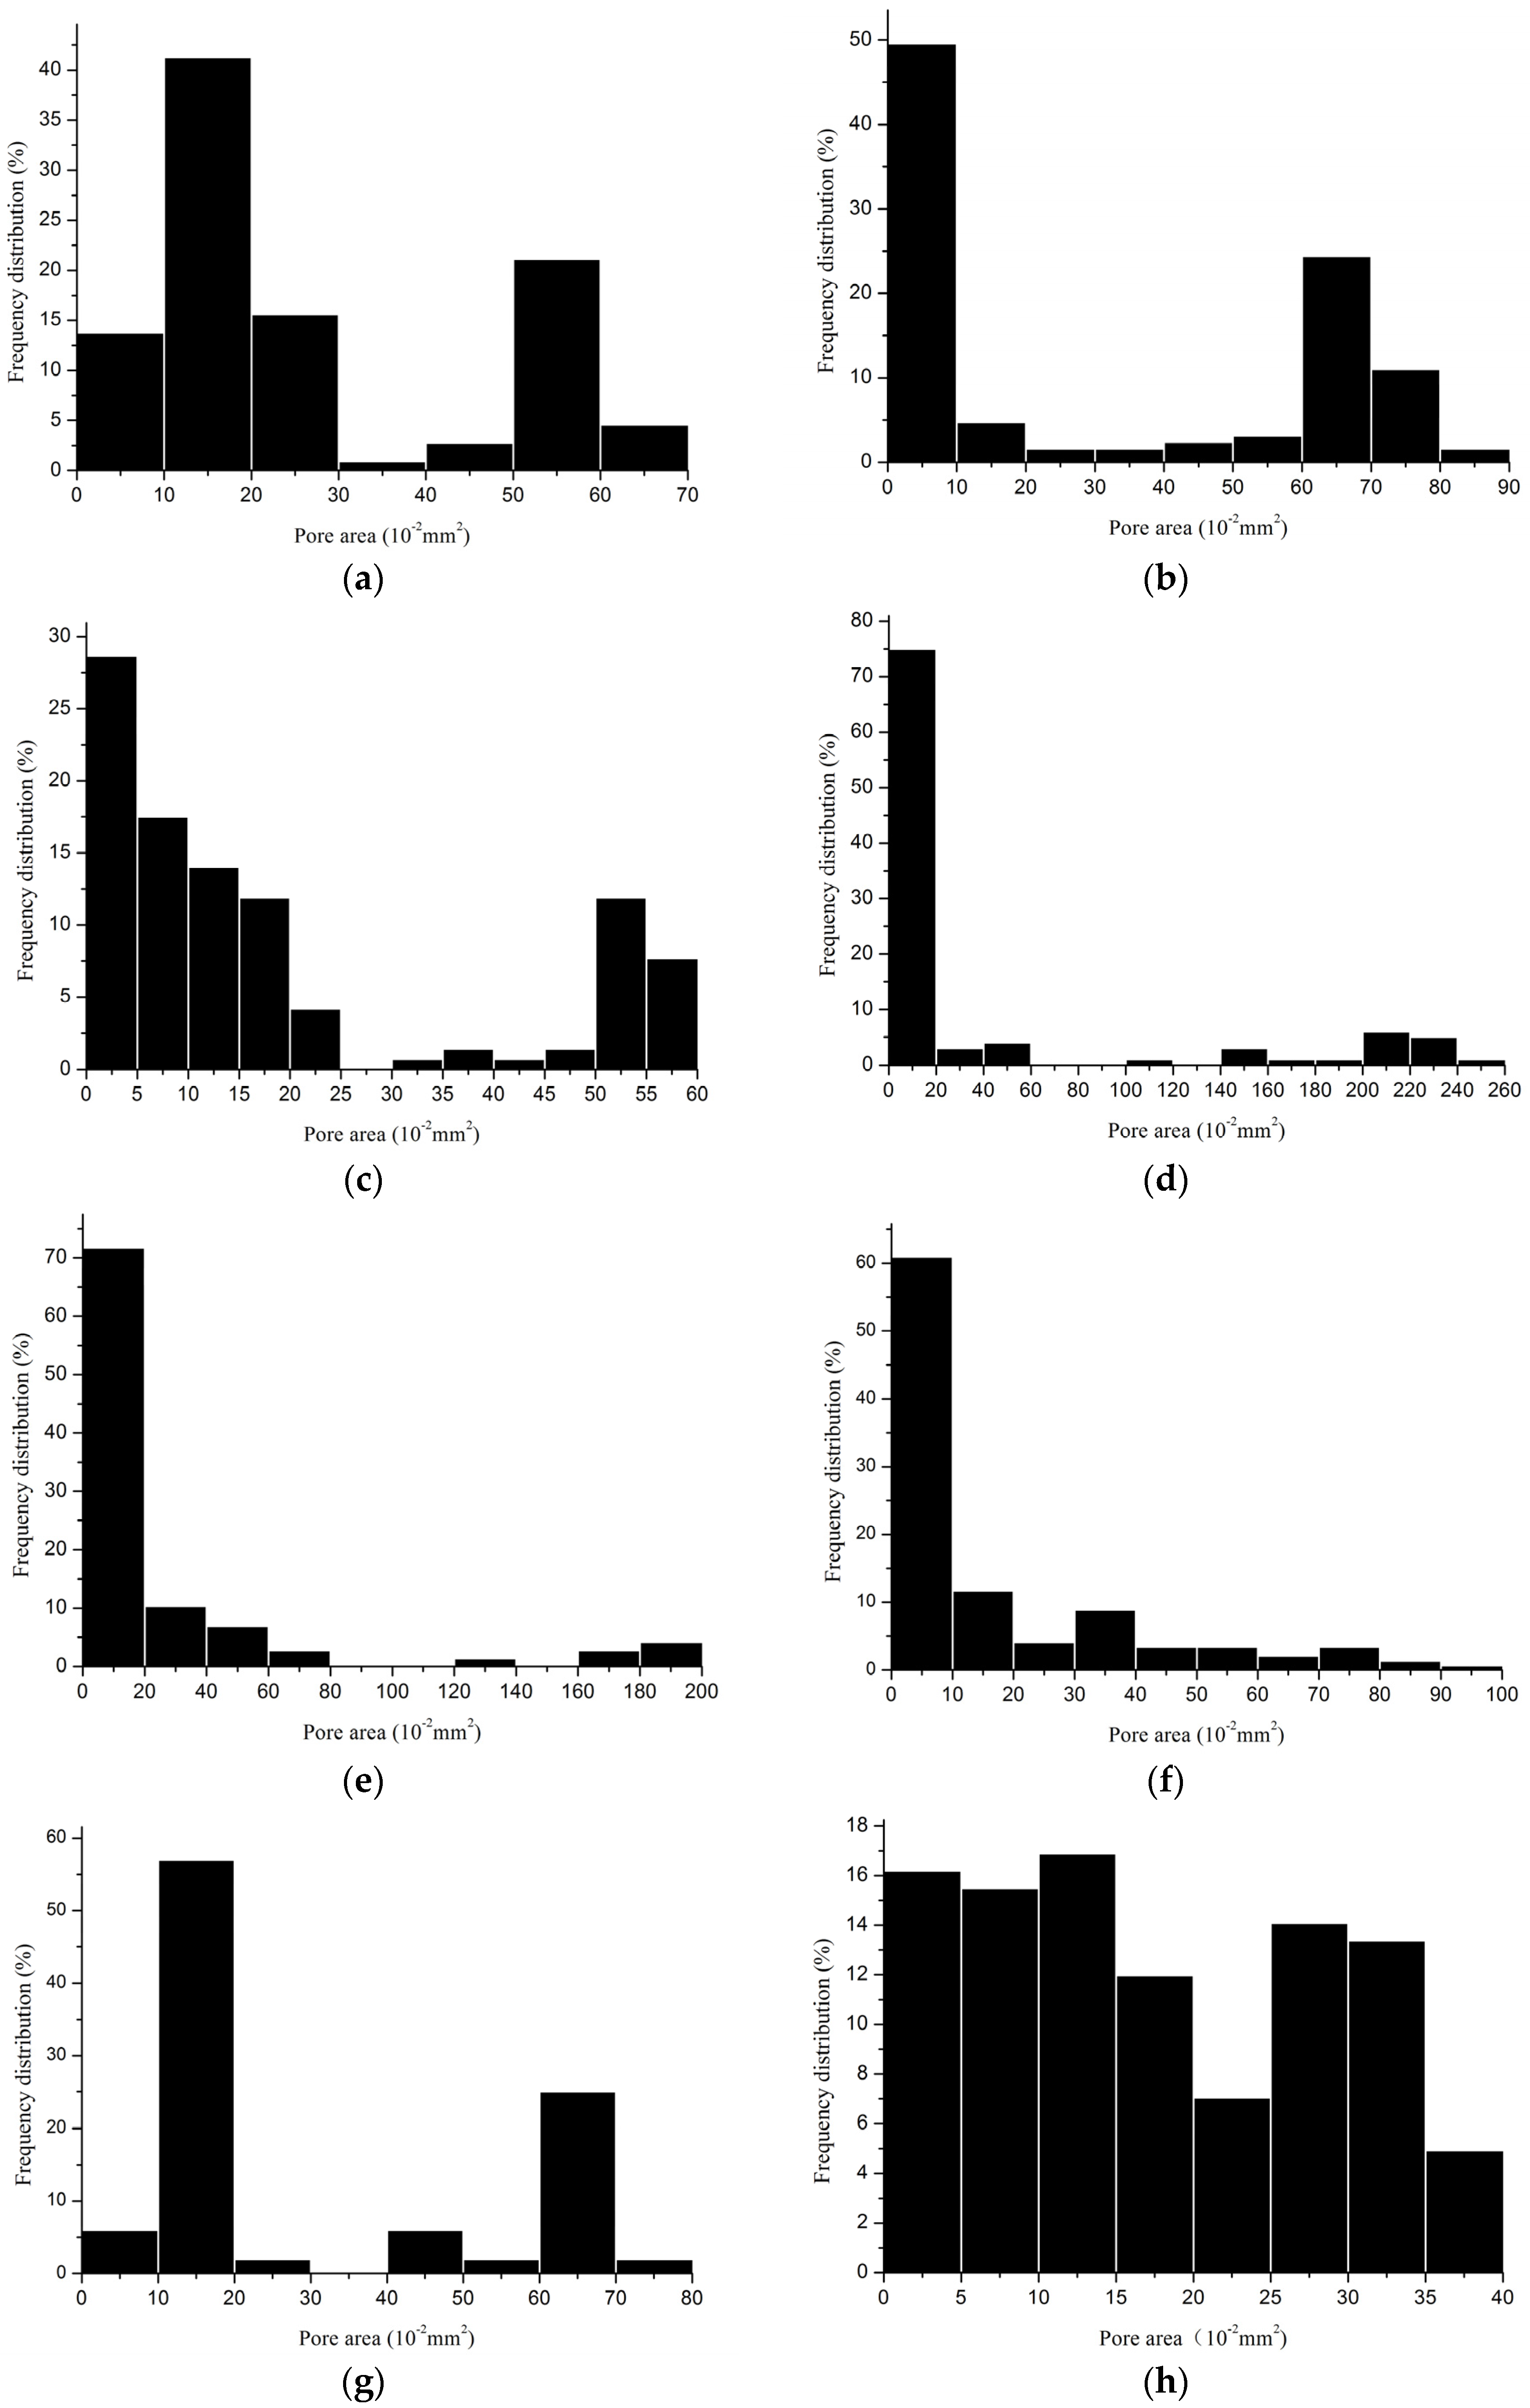

2.2.3. Porosity

| Device | Minimum Pore Size (mm2) | Maximum Pore Size (mm2) | Porosity (%) | Porosity I * (%) |

|---|---|---|---|---|

| 1 | 0.0007 | 0.6500 | 42.6 | 0 |

| 2 | 0.0018 | 0.8700 | 61.7 | 5.9 |

| 3 | 0.0040 | 0.5899 | 40.5 | 0 |

| 6-1 | 0.0065 | 0.9827 | 44.4 | 5.1 |

| 6-2 | 0.0096 | 0.7300 | 42.1 | 0 |

| 7 | 0.0012 | 0.3916 | 37.3 | 0 |

| Device | Minimum Pore Size (mm2) | Maximum Pore Size (mm2) | Porosity (%) | Porosity I * (%) |

|---|---|---|---|---|

| 4 | 0.0042 | 2.400 | 64.2 | 54.7 |

| 5 | 0.0044 | 1.900 | 58.2 | 30.8 |

| 8 | 0.0052 | 1.2517 | 60.1 | 46.2 |

| 9 | 0.0013 | 1.5776 | 69.2 | 60.1 |

3.2. Pore Characteristics

3.3. Why Can the Same Lapping Structure Lead to Different Pore Characteristics?

3.4. Which Method Could Be Most Effective in Characterizing the Pore Size of Hernia Prostheses?